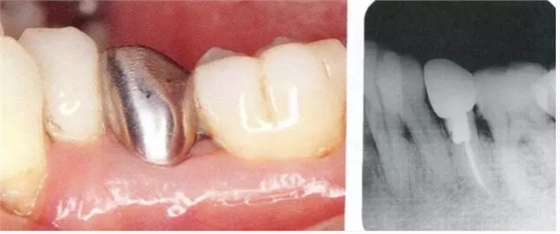

▲圖18-1,2

▲圖18-1 左下5佩戴金屬冠,但是由于近遠中接觸點的位置和大小不合適,導致鼓形間隙基本消失。

▲圖18-2 同部位的X光片??梢钥吹烬l下有牙結石沉積,并且有牙槽骨吸收現(xiàn)象。